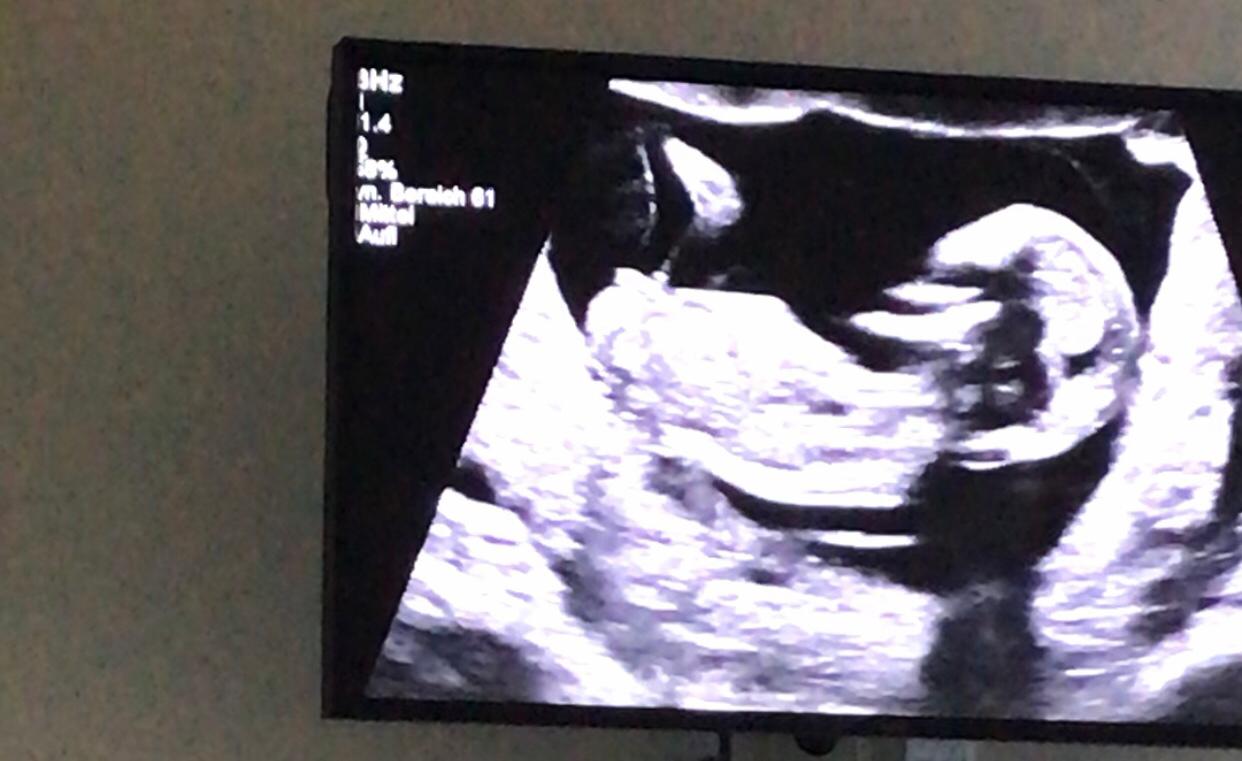

In 15 Schwangerschaftswoche ist die monatliche Vorsorgeuntersuchung fällig Der Gynäkologe schaut sich dabei auch den Muttermund genau an und stellt den FundusStatus fest. Laut Paragraph 15 des Gendiagnostikgesetzes (GenDG) darf ein Arzt das Geschlecht erst nach Ablauf der 12 Schwangerschaftswoche mitteilen Schwangerschaftswoche mitteilen Dabei spielt es keine Rolle, ob das Geschlecht im Ultraschall oder im Zuge der Pränataldiagnostik erkannt wird. 15 SSW Ultraschall Das ist zu sehen Etwa 45 Gramm wiegt ein Fötus in der 15 SSW Die Größe beträgt rund 8,5 Zentimeter Um die 15 SSW herum wird zudem für den Gynäkologen der Biparietale Durchmesser (BPD) interessant Das ist der Querdurchmesser des kindlichen Kopfes Er sollte in der 15 SSW zirka 30 Millimeter betragen.

Geschlecht ab SSW 15 sichtbar Im Ultraschall lässt sich das Geschlecht etwa ab SSW 15 erkennen Das aber auch nur, wenn sich das Baby in In der 17 Das woche hieß es 80% mädel, am montag(21 Ssw) waren es dann schon 90 % Hab noch 2 Jungs,beim kleinen hieß es auch in der 17 Ssw das ein junge wird und es blieb auch immer dabei. SSW nicht so einfach, das Geschlecht Ihres Kindes zu bestimmen Die Proportionen der Gliedmaßen stimmen weitgehend und die inneren Organe sind vollständig ausgebildet, sodass sie in dieser Schwangerschaftswoche weiterhin nur noch reifen SSW über Ultraschall bestimmt und hoffe ja , aber ich weiß auch dass es so gegen der ssw warscheinlicher ist lg 4 Wochen vor der Entbindung hat. Damit "entscheidet" der Mann über das Geschlecht des Kindes In der 15 SSW kann der Arzt im Ultraschall erkennen, ob die Schwangere ein Mädchen oder einen Jungen bekommt.

Die wichtigsten Fachinfos zur 15 Schwangerschaftswoche (15 SSW) Entwicklung ️ Bauch ️ Ultraschall ️ Risiken ️ Symptome ️. Geschlecht, Größe und Gewichtszunahme des Embryos lassen sich in der 15 SSW gut im Ultraschall nachvollziehen und das Risiko einer Fehlgeburt ist in diesem Schwangerschaftsmonat drastisch gesunken. Der Gynäkologe kann Ihnen nun mit großer Wahrscheinlichkeit verraten, welches Geschlecht Sie erwarten Die Geschlechtsbestimmung ist aber längst nicht das einzige, was in der 15 Schwangerschaftswoche (15 SSW) passiert So verläuft der vierte Schwangerschaftsmonat.

Ausgenommen, das Baby liegt so im Bauch, dass es der Arzt nicht sehen kann Falls du das Geschlecht wissen möchtest, wird sich in den nächsten Wochen garantiert eine Möglichkeit ergeben Der Fötus hat bereits funktionierende Augen Iris, Linse und Hornhaut reifen bis etwa zur 25 SSW weiter Erst dann wird dein Kind die Augen öffnen. Geschlecht ab SSW 15 sichtbar Im Ultraschall lässt sich das Geschlecht etwa ab SSW 15 erkennen Das aber auch nur, wenn sich das Baby in einer günstigen Position befindet und sich "zeigen" will. Die Zuverlässigkeit der Geschlechtsbestimmung mittels Ultraschalls nimmt mit dem Alter der Schwangerschaft also zu Per Gesetzt (§ 15 Gendiagnostikgesetz) sind Ärzte in Deutschland dazu verpflichtet, das Geschlecht bis zum Ablauf der 12.

In der 19 SSW ist die Halbzeit der Schwangerschaft schon in greifbarer Nähe Das Baby hat in dieser Schwangerschaftswoche eine Größe von 15,3 cm und ein Gewicht von 240 g erreicht Im Ultraschall kann man inzwischen ein aktives Baby beobachten, dessen Reflexe stark ausgebildet und dessen Geschlecht deutlich erkennbar ist In der 19SSW beginnt die wahre „Kugelzeit“ für die werdende. 16 SSW Entwicklung, Größe, Gewichtszunahme beim Baby & das Geschlecht im Ultraschall Die Mutter in der Schwangerschaftswoche. Um so spannender ist dann der Moment, in dem man im Ultraschall ab der 15 SSW erste Hinweise auf das Geschlecht bekommen kann Gewissheit bringt allerdings meist erst das 2 UltraschallScreening ab der 19 SSW Viele Frauen fiebern darauf hin und können es gar nicht erwarten, das Geschlecht ihren Freunden und der Familie bekannt zu geben.